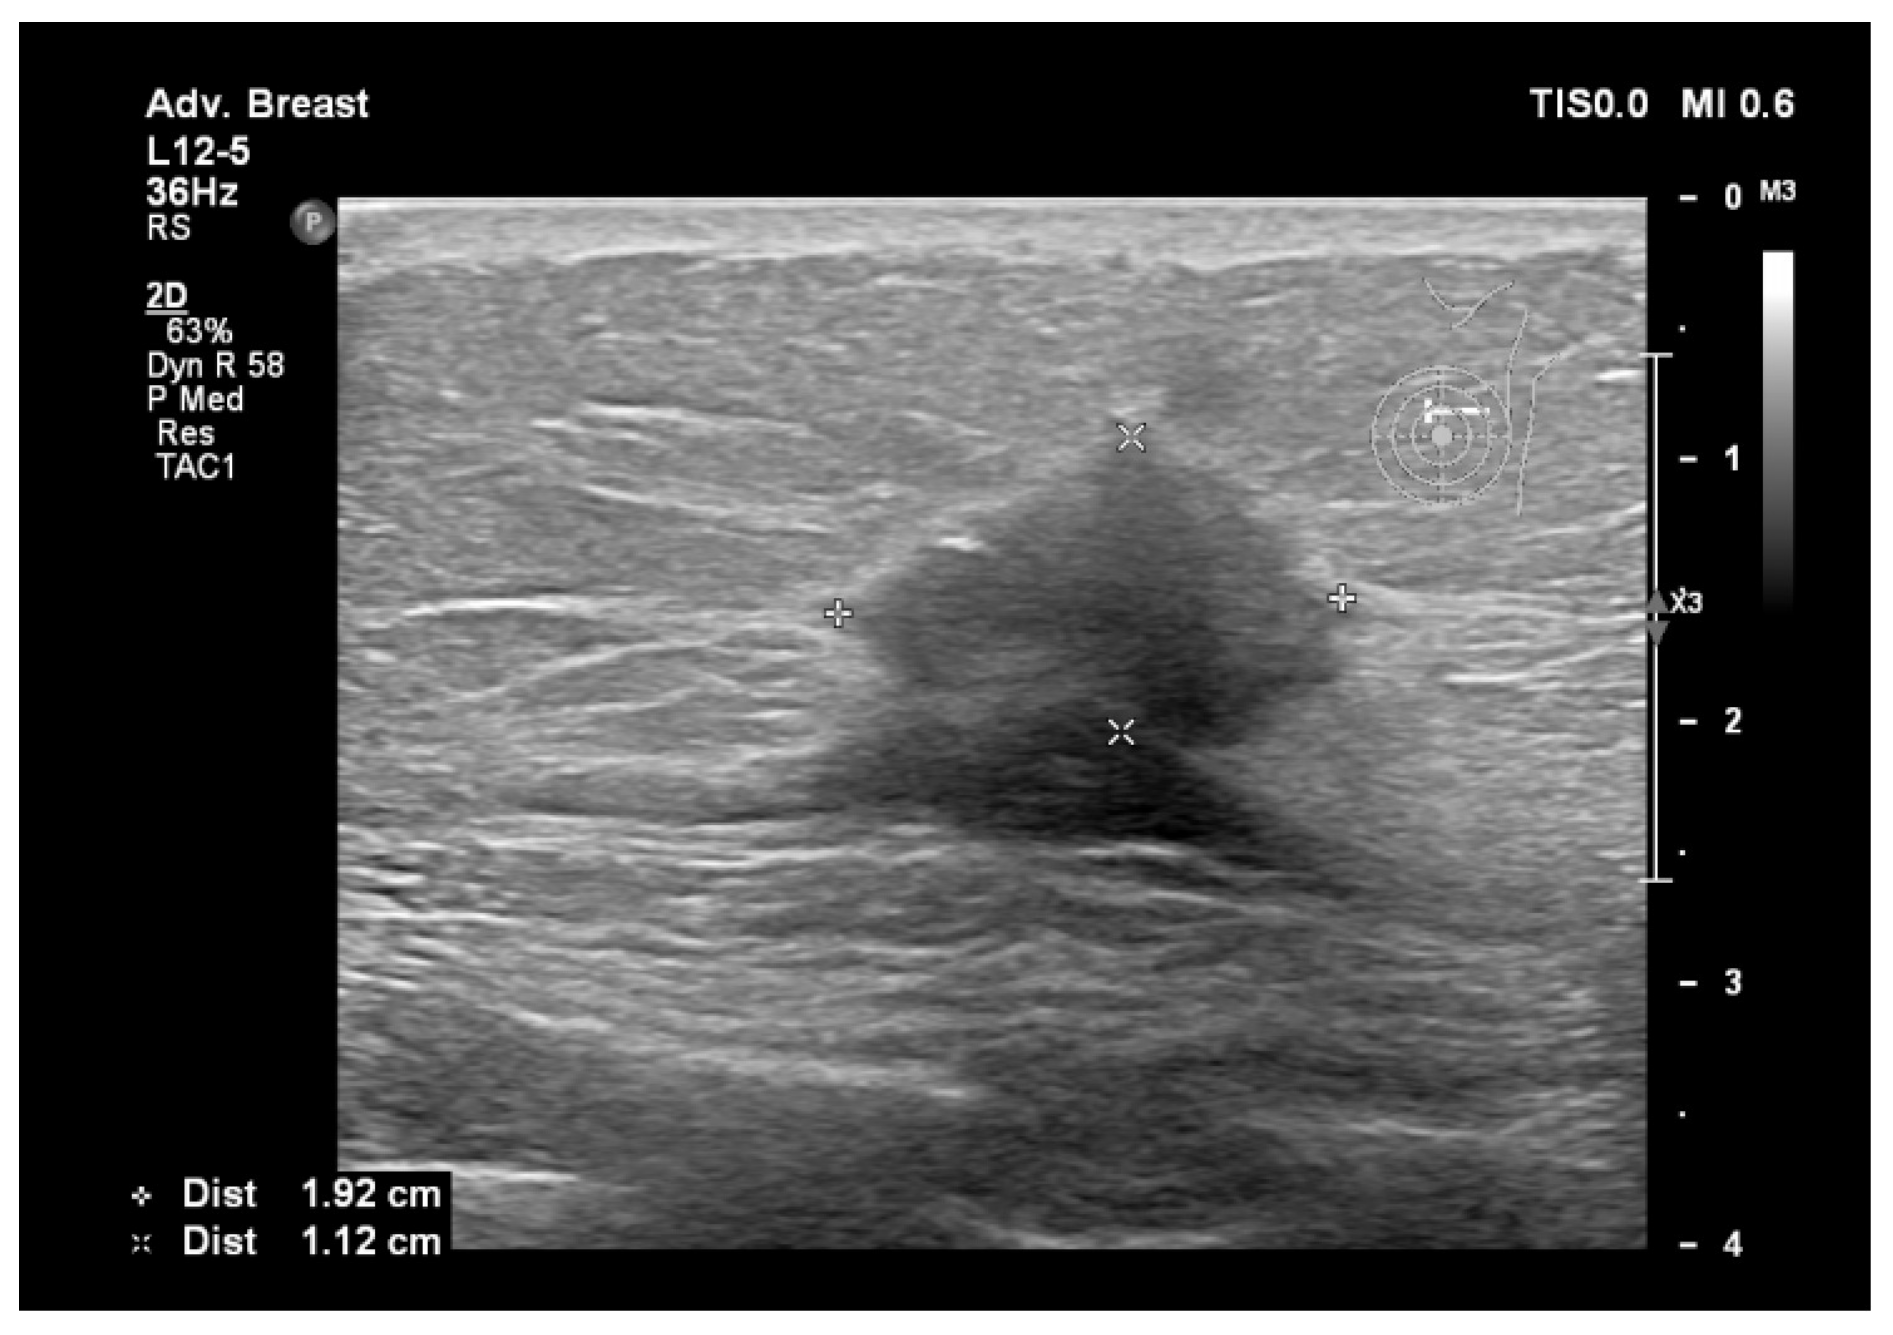

6.1. Characterization of Lesions

6.2. Real-Time Imaging and Guided Biopsies